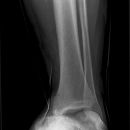

Totale Talusluxation

Talus Fraktur

Snowboard fracture Talus